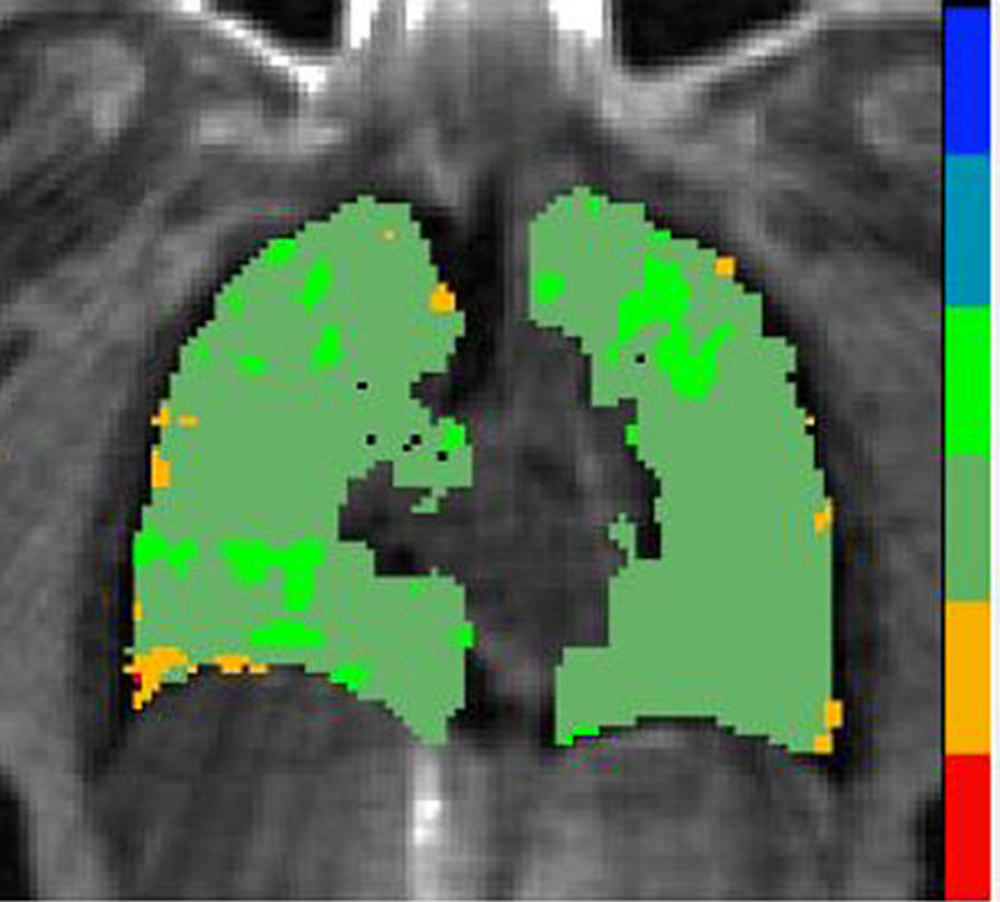

Figure 3. Gas exchange map - High

High-res (TIF) version

Figure 2. Individuals in the study are plotted with x-axis being rank of pulmonary gas exchange. The black dots show the pulmonary gas exchange ratio, which in this case is the red blood cell to tissue plasma ratio (RBC:mem), on the left y-axis and the blue dots are the cognition scores on the right y-axis. Gas exchange maps of three representative patients from a low, medium and high pulmonary gas exchange.